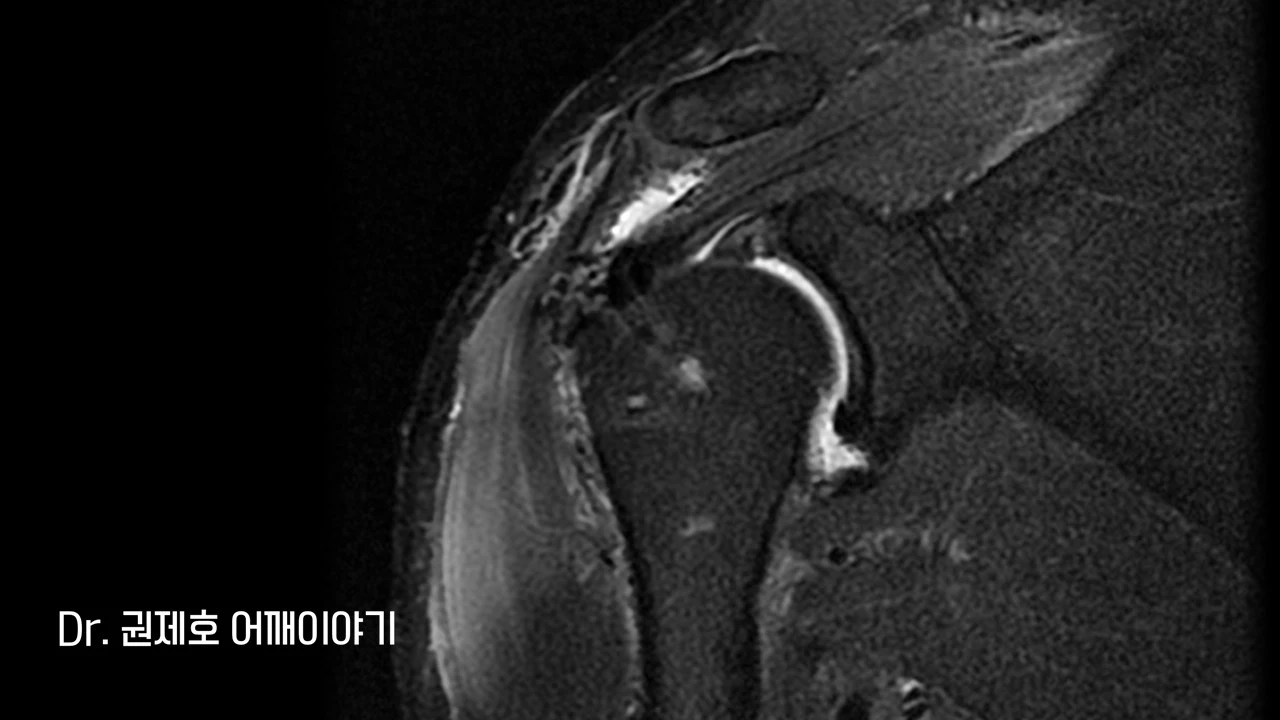

어깨 MRI를 검사하는 이유는 어깨 주변을 객관적으로 판단하기 위함이다. 거의 100장에 가까운 사진을 이 각도, 저 각도에서 찍고, 이를 모두 한꺼번에 보면서 판독을 하는데, 가장 대표적인 사진 한 장 만을 추렸다.

MRI에서 보면 회전근개 (어깨 인대)가 끊어지면서 속으로 말린 현상이 보였으며, 끊어진 부위는 헤진 상태였다.